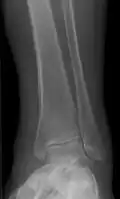

Periosteal reaction from venous stasis -

Periosteal reaction from venous stasis